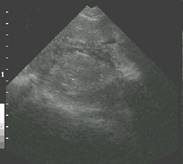

Non-pregnant uterus Ovarian Follicles and uterine outline Sow in estrus